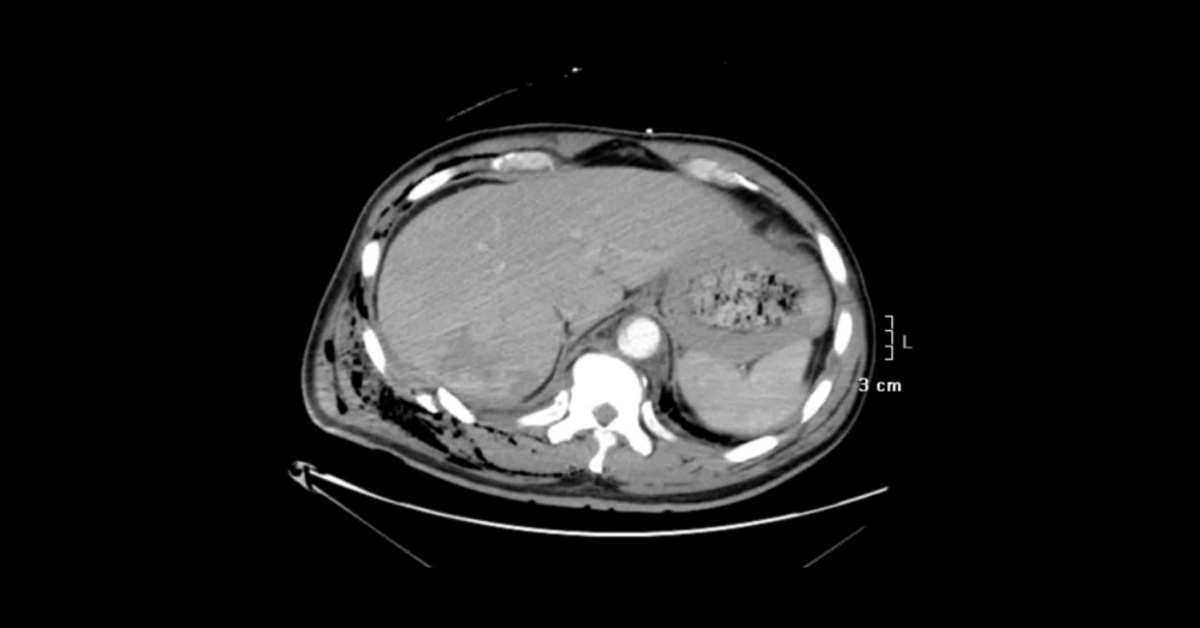

Presented by Ashish Khandelwal, MBBS, MD at Practical Radiology 2025. This talk will allow you to understand appropriate use of multimodal imaging in pregnant patient and know the imaging features of commonly encountered acute abdominopelvic conditions during pregnancy.